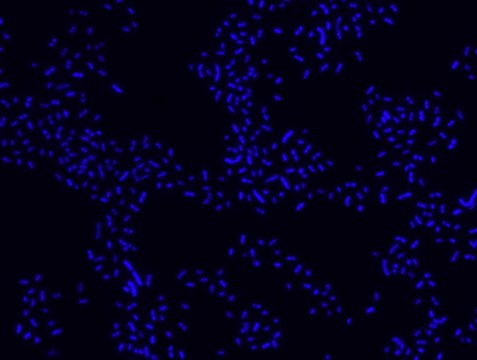

Proteus probe specifically recognizes Proteus species (see images of Proteus vulgaris and Proteus mirabilis). Moreover, it was shown that this probe recognizes Proteus penneri and Proteus hauseri.16

FISH technique was successfully used for clinical detection of Proteus spp. in artificial urine medium and urine samples from patients with UTIs. The probe was able to detect 11 strains of P.mirabilis, 6 strains of P. vulgaris, 2 strains of P.penneri and one strain of P. hauseri.16 The probe can also be used to detect P. mirabilis and P. vulgaris pure culture (as described in the figure legends). FISH can also be implicated to detect Proteus spp. in colon sections embedded in paraffin.17,18 Moreover, FISH can be implicated to identify Proteus spp. in the gut of the medicinal leech.19

Probe for fluorescence in situ hybridization (FISH),recognizes Proteus vulgaris and Proteus mirabilis cells.